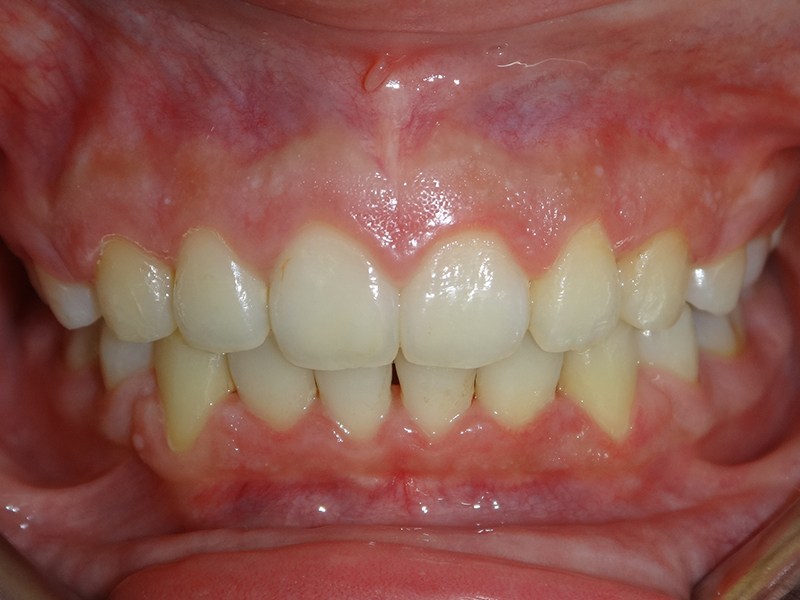

隱適美拔牙改臉型(二) 首頁 案例分享 齒顎矯正 隱適美拔牙改臉型(二) 拔牙改臉型案例 年紀:20 歲 女性 治療方式:隱適美隱形矯正 時間:29個月 主訴:外觀看起來比較暴,希望可以把牙齒排列整齊以及後縮 矯正前 矯正後 矯正前 矯正後 矯正前 矯正後 聲明:本所療程皆由專業醫生評估後,依照個人口腔狀況進行治療。因每位患者個別狀況不同,術後狀況也不盡相同,需親來本所由醫生評估。